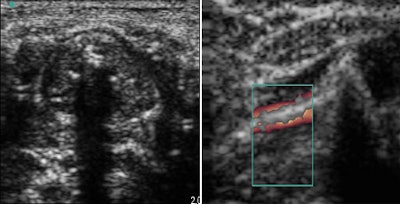

![]() |

| Posterior shadowing indicates tracheal intubation (left). Sliding sign confirms tube position (right). |

While confirmation of the tube position was obtained in all cases by the sliding lung sign, the final visualization of the tube in the trachea was not always easy, the group stated, adding that the culprit was most likely interference between the echogenic characteristics of the tracheal ring and the tube. Doppler ultrasound may be one solution to improving tube visualization, Marciniak said.

As with sonography in general, successful visualization of the tube is operator-dependent. However, Marciniak told AuntMinnie.com that the learning curve for ultrasound-based tube visualization is quite low because it does not require as much technical precision as a diagnostic ultrasound.